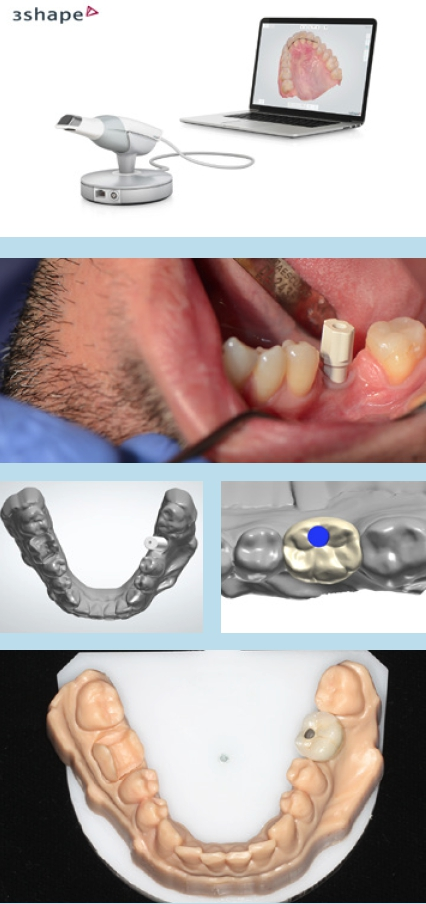

Abformung

Parallel kann schon mit dem Abutmentdesign begonnen werden. Dabei ist es unerheblich, ob es sich um eine verschraubte oder zementierte Versorgung handelt. Mehrgliedrige verschraubte Arbeiten sollten mit einer Schlüsselprobe geprüft werden, um Spannungen auszuschließen. Die Limitation des Scanverfahrens liegt im Aneinanderfügen vieler Einzelbilder. Das Risiko für Dimensionsabweichungen steigt somit mit der Größe bzw. Weitspannigkeit der geplanten Restauration.

Unabhängig, ob digital oder analog vorgegangen wird, ist bei der Einbringung der Abformpfosten bzw. Scanbodies darauf zu achten, dass diese sich nicht berühren oder die Nachbarzähne touchieren. Liegen Freilegung und Implantation zeitlich weit auseinander und wurde die Lücke nicht provisorisch versorgt, kann es zum Aufwandern der Nachbarzähne kommen (Abb. 14–17). In diesem Fall ist es notwendig, die Abformpfosten zu beschleifen oder das Aufwandern kieferorthopädisch zu behandeln.